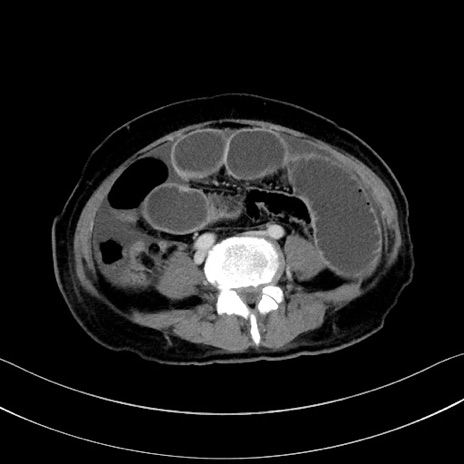

症例28(横断像)

【症例】60歳代男性

【主訴】嘔吐

【現病歴】胃癌にて胃全摘後。食思不振が悪化し、夜中に嘔吐することがある。

【既往歴】胃癌、胃全摘、脾摘、胆摘後

【データ】WBC 5900、CRP 10.56